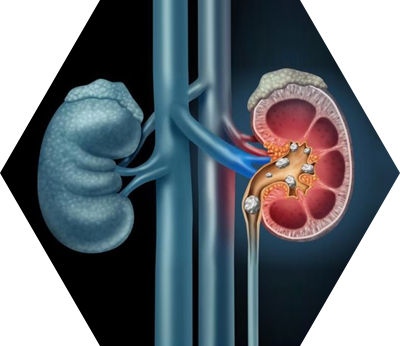

Kidney stones (renal lithiasis, nephrolithiasis) are urinary deposits